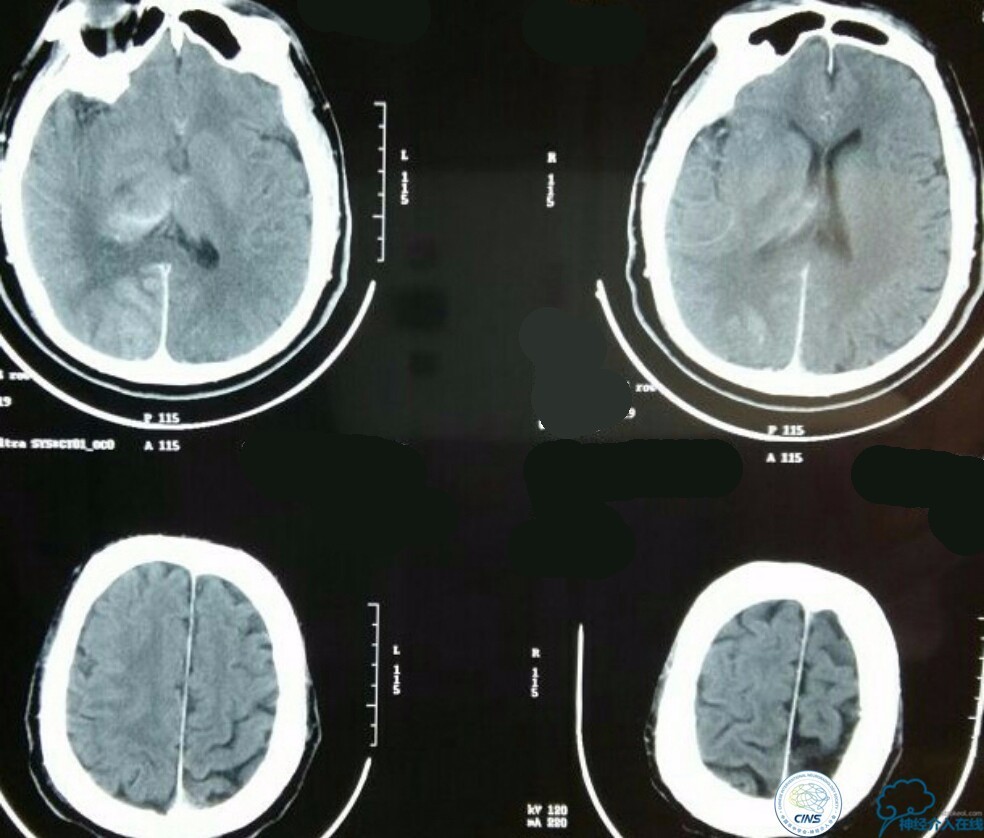

查体:浅昏迷,双侧瞳孔不等大,D右:D左=3.0:1.5mm,对光反射消失,左侧鼻唇沟变浅,左眼闭合不全,左侧肢体肌力0级,左侧病理症(+),其余查体不能配合,内科查体无异常。NIHSS评分:20分,心电图:正常心电图,随机血糖:17mmol/l,头颅CT:未见异常。

急诊MRI+MRA:右侧丘脑及小脑半球多发新鲜梗死病灶,右侧颈内动脉颅内段未见显影,基底动脉尖未见显影!

术后生命体征平稳,告捷撤呼吸机,肌力较前好转,复查头颅CT:

右侧丘脑高密度影,右侧枕叶可能也有梗死,祈祷慢慢恢复吧!